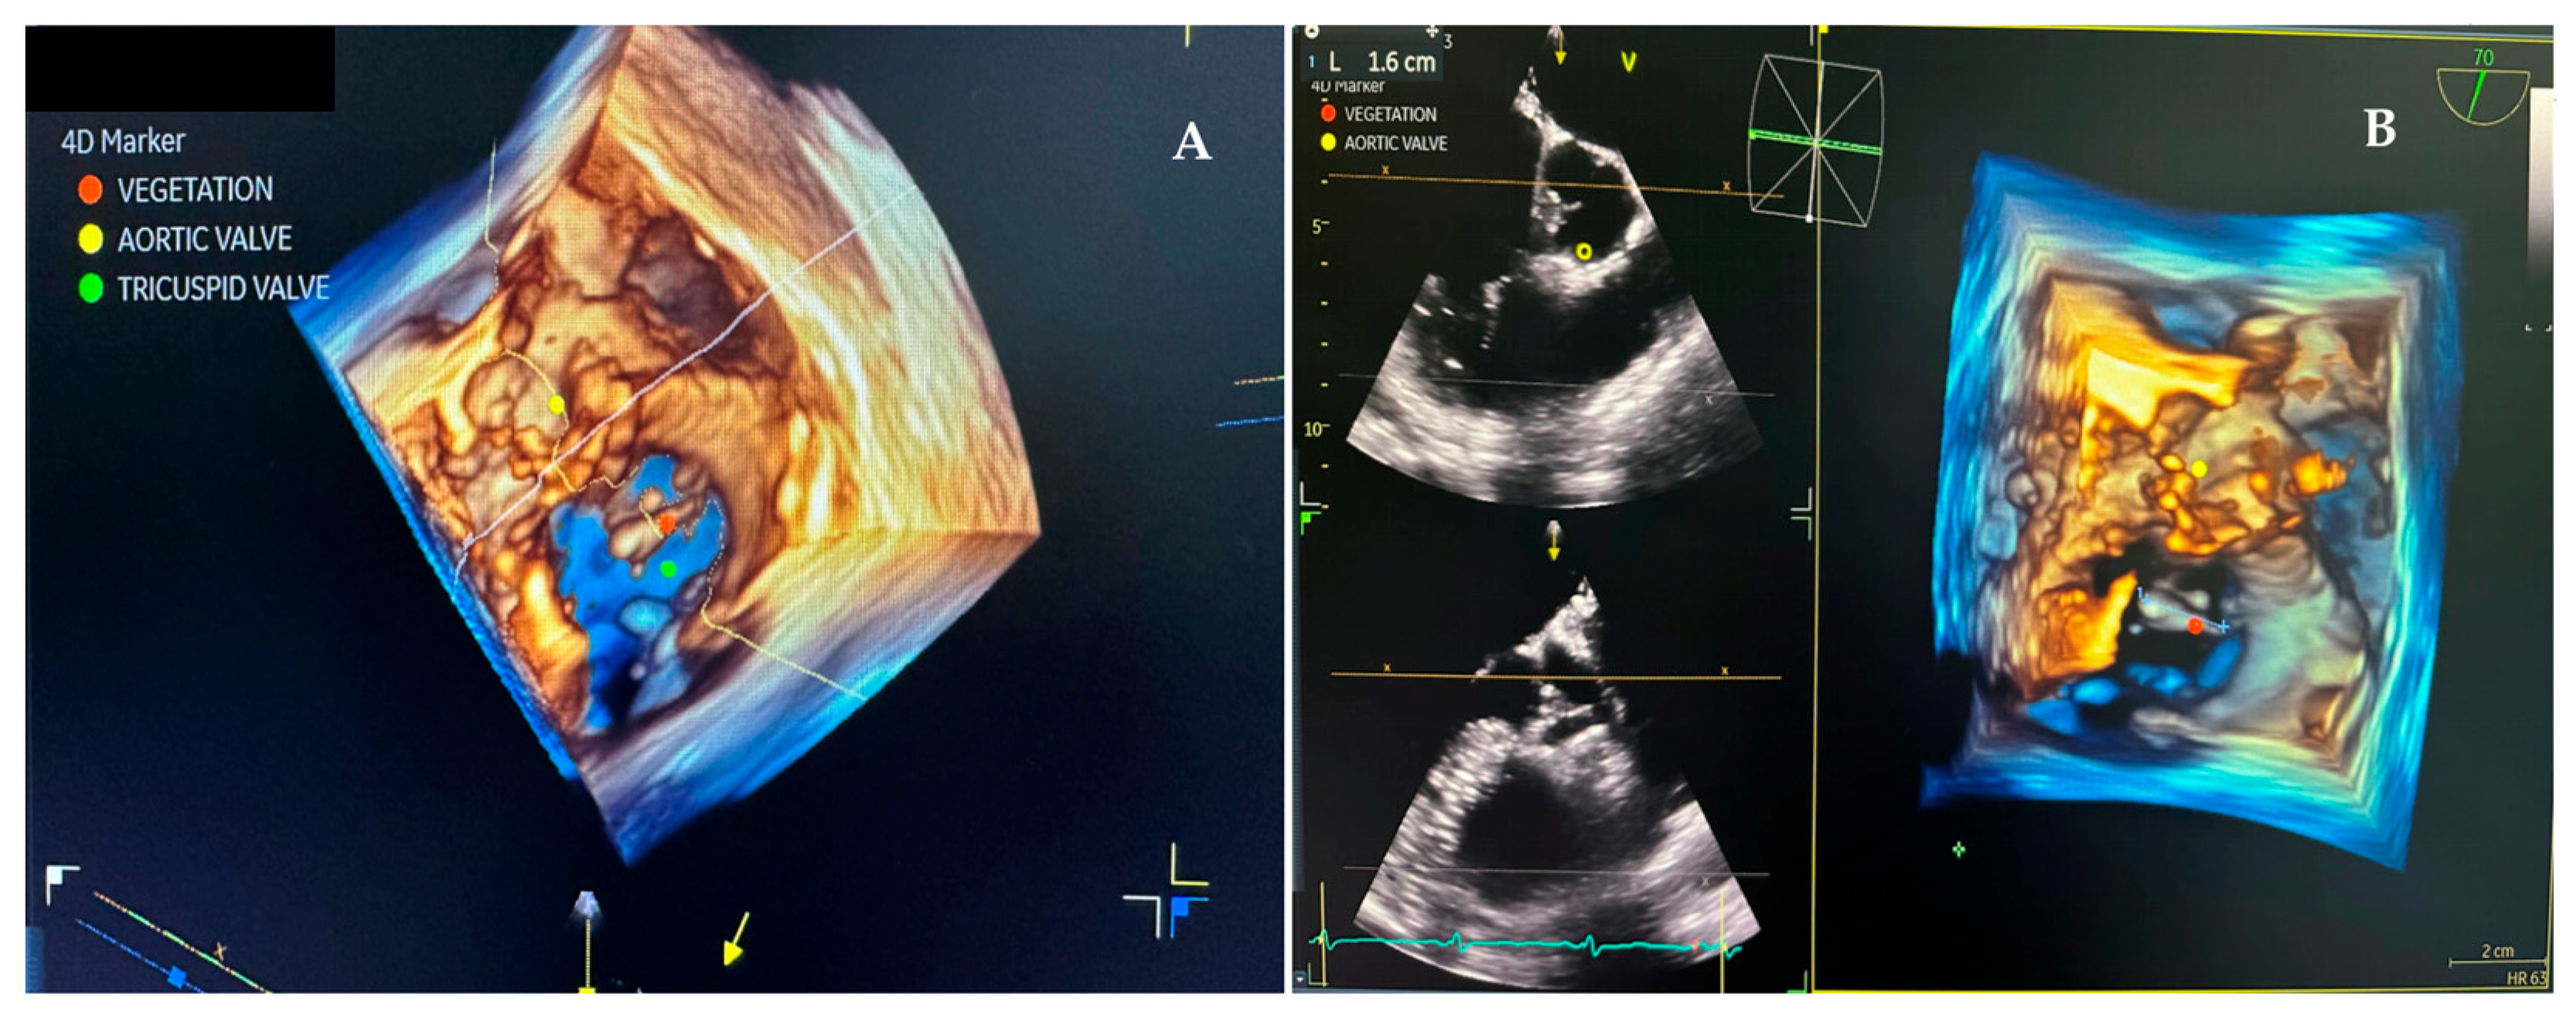

2. Case Presentation